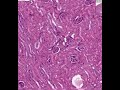

Shotgun Histology Appendix

Video Tags:Appendix, Histology, Shotgun